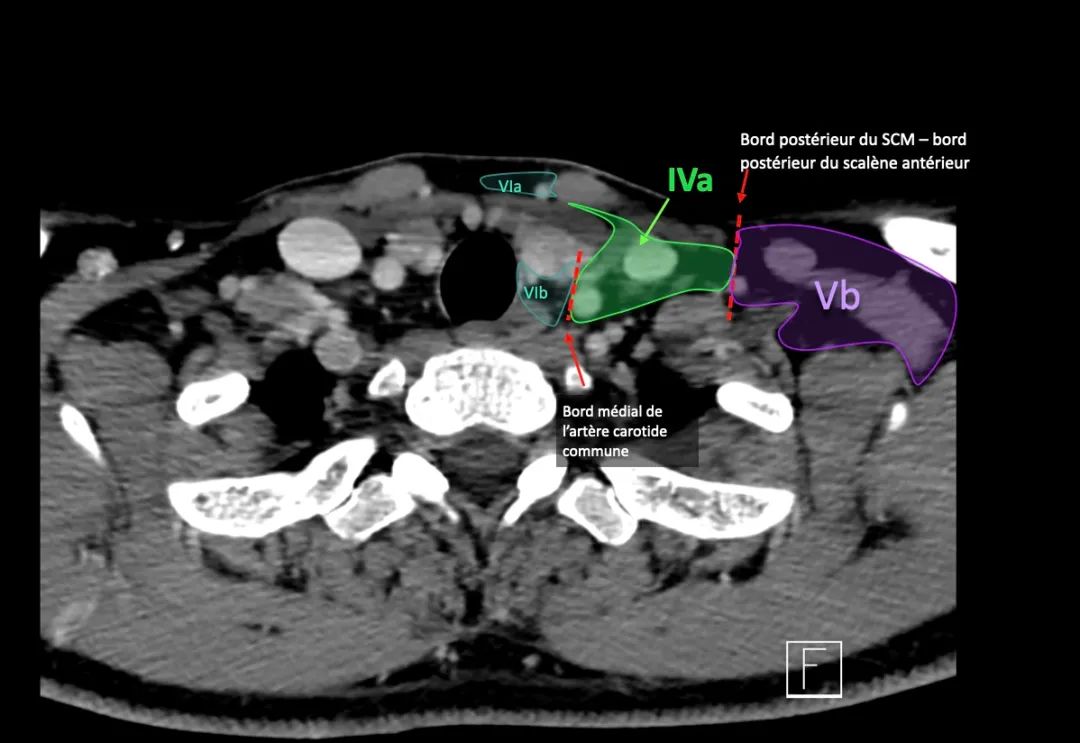

IVa和IVb水平之间的边界设置在距胸锁关节2 cm的颅侧。

IVb级

这些淋巴结有隐藏来自下咽部、声门下喉、气管、甲状腺和颈段食管的癌症转移的风险。

这一层包括浅表的颈前淋巴结(VIa层)和较深的喉前、气管前、气管旁和喉返神经淋巴结(VIb层)。

VIb

该水平包含在颈总动脉的内侧边界之间。

该区域中的节点有: